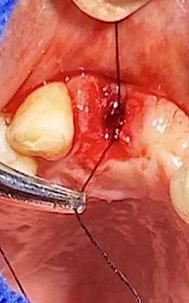

Figura 7. Exodoncia de la unidad dental, revisión del alveolo, curetaje y retiro de exudado purulento con cucharilla de lucas.

Elaboración: Los autores.